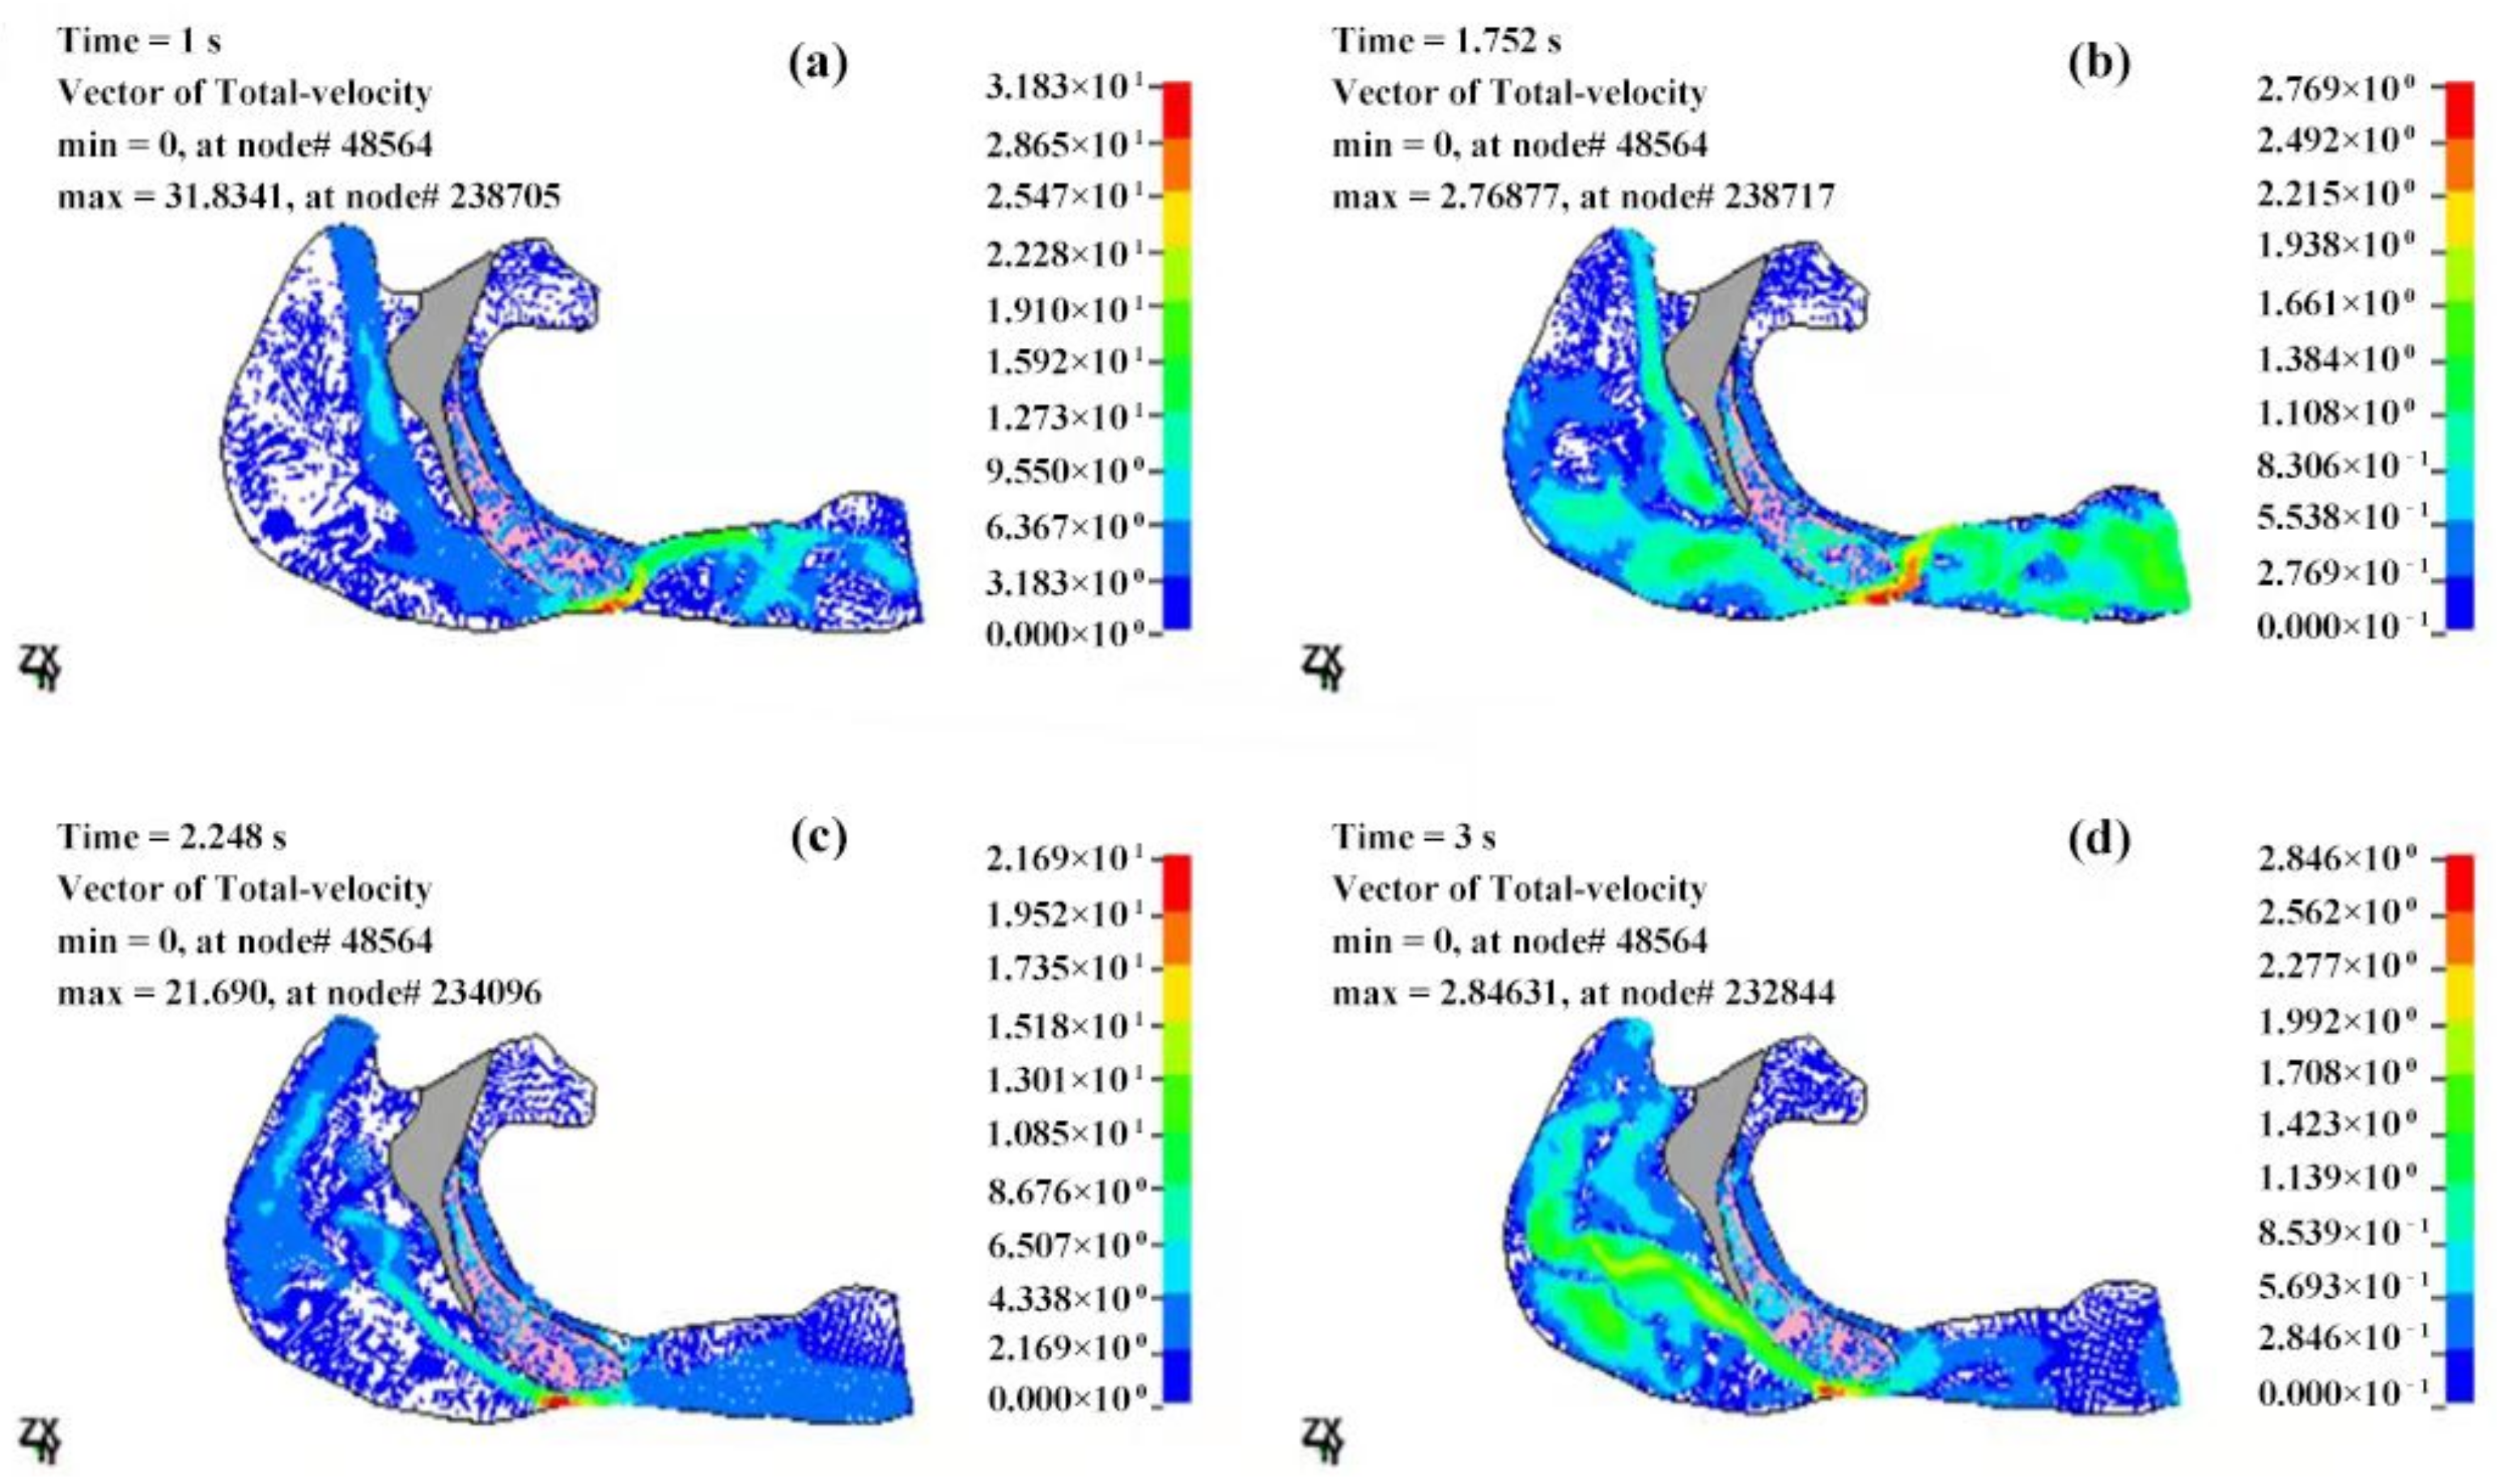

3.2.2. Velocity Field of the Cavity

4. Discussions

- The airflow characteristics during the inhalation phase are noticeably different from those in the exhalation phase for both eupnea and apnea. As the OSAHS patient breathes, the minimum pressure occurs alternately between the soft palate and the anteroposterior wall of pharynx, which causes the soft palate to vibrate during respiration, and therefore, the patient snores in sleep.

- The mechanical environment of the airway is directly dependent on the action of the airflow. If the mechanical properties of the soft palate remain unchanged, the pressure makes the soft palate collapse in apnea. In eupnea, the pressure allows the airflow to pass freely through the airway.

| T (s) | Pmax (Pa) | Pmin (Pa) | ΔP (Pa) | Pressure Drop (Pa) |

|---|---|---|---|---|

| 0.5 | 101,332 | 100,945 | 387 | −201 |

| 1 | 101,337 | 100,709 | 628 | −302 |

| 1.25 | 101,333 | 100,960 | 373 | −201 |

| 1.5 | 101,329 | 101,127 | 202 | −98 |

| 1.75 | 101,327 | 101,321 | 6 | 1 |

| 2 | 101,429 | 101,258 | 171 | 99 |

| 2.5 | 101,533 | 101,225 | 308 | 198 |